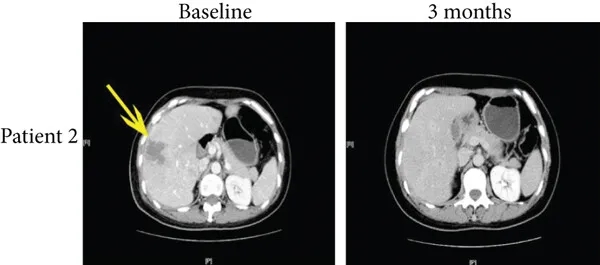

病例2为一例50岁患者,治疗前存在肝转移,经4个月免疫联合治疗后,多发性肝转移达到完全缓解(详见下图,黄色箭头所示),PFS达10.9个月。

▲图源“J Immunol Res”,版权归原作者所有,如无意中侵犯了知识产权,请联系我们删除